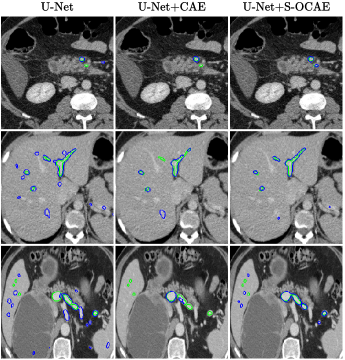

Refer to caption

Fig. 3: Liver vessel segmentation results. Ground truth and predicted contours are respectively in green and blue.

U-Net [4] using VGG13 with BN pre-trained on ImageNet as encoder [6] was compared with the same U-Net architecture complemented with shape priors from either a standard CAE (U-Net+CAE) [12] or the proposed S-OCAE (U-Net+S-OCAE). Both auto-encoders were trained from scratch.

Quantitative results (Tab.1) indicate that adding shape priors to U-Net significantly improves delineation results in all assessment metrics. Moreover, whatever the dataset, the proposed method outperforms U-Net+CAE in DSC, AVD, ASSD, and HD except for 3D-IRCADb where U-Net+CAE reaches a slightly better DSC. The main improvement from U-Net+CAE to U-Net+S-OCAE is observed at the level of the HD metric which undergoes a rise of 3.08%percent3.083.08\% for DRIVE and 4.03%percent4.034.03\% for 3D-IRCADb. The attenuation of the largest segmentation errors suggests that vessel contours provided by U-Net+S-OCAE are more suitable with respect to clinical requirements. Results without and with CB reveal the positive impact of making communicate under and overcomplete features. In addition, vessel delineations displayed in Fig.3 and 4 highlight a better ability of U-Net+S-OCAE to extract small structures against other methods, while providing less false positives. These results tend to indicate that relying on a semi-overcomplete embedding to produce shape priors leverages a robust representation of the vascular tree geometry, despite the large range of various multi-scale structures visible in both DRIVE and 3D-IRCADb datasets.